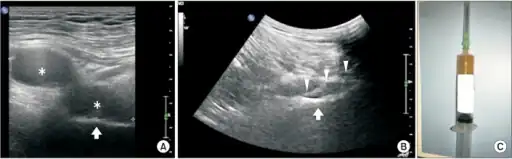

- High-frequency ultrasonography to identify the location of pudendal nerve compression.

- Doppler ultra sound to detect vein compression, a result of nerve compression.[25]

Imaging studies using MR neurography may be useful. In people with unilateral pudendal entrapment in the Alcock's canal, it is typical to see asymmetric swelling and hyperintensity affecting the pudendal neurovascular bundle.[29]